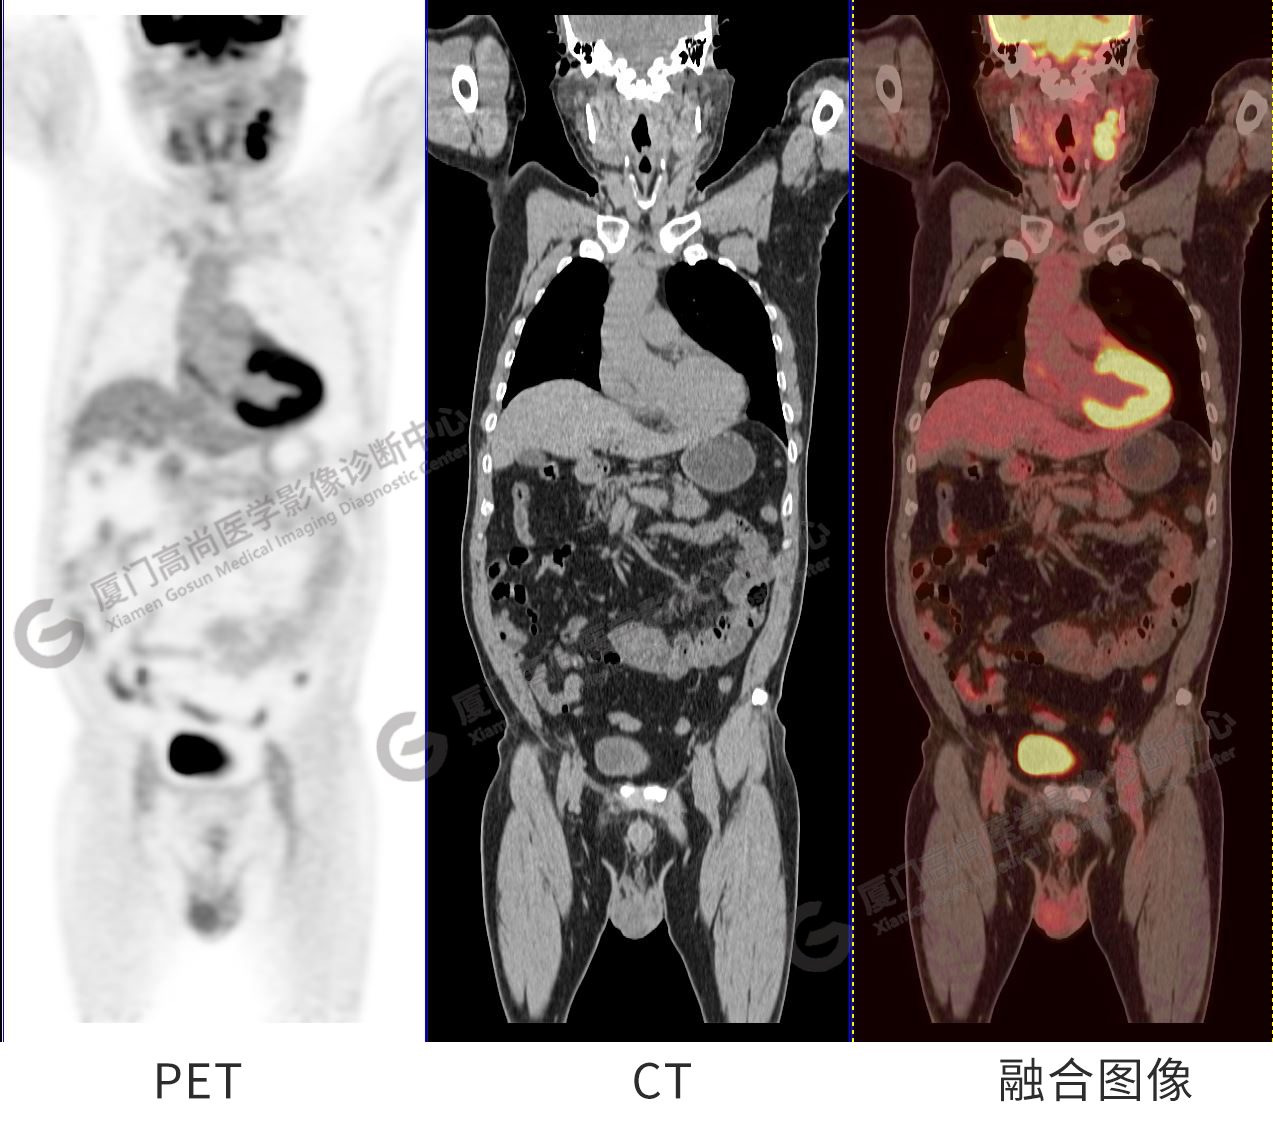

圖1:PET/CT全身圖像

圖2-9:雙側(cè)鎖骨區(qū)、縱隔、右側(cè)內(nèi)乳區(qū)、腸系膜緣、腹膜后、雙側(cè)髂血管旁及盆腔多發(fā)腫大淋巴結(jié)影,代謝不同程度增高,考慮為轉(zhuǎn)移。

圖10-11:子宮頸軟組織腫塊,代謝異常增高,考慮為宮頸癌。

圖12-13:延遲2小時后,宮頸腫塊糖代謝進一步增高。